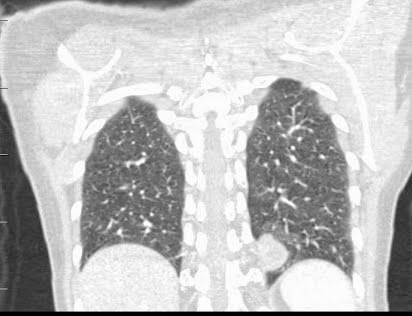

CASO 2 (CGC)

Varón de 33 años que ingresa por cuadro de fiebre de hasta 40º de 1 semana de evolución sin tos , expectoración ni disnea.

caso aportado por ARD

solución